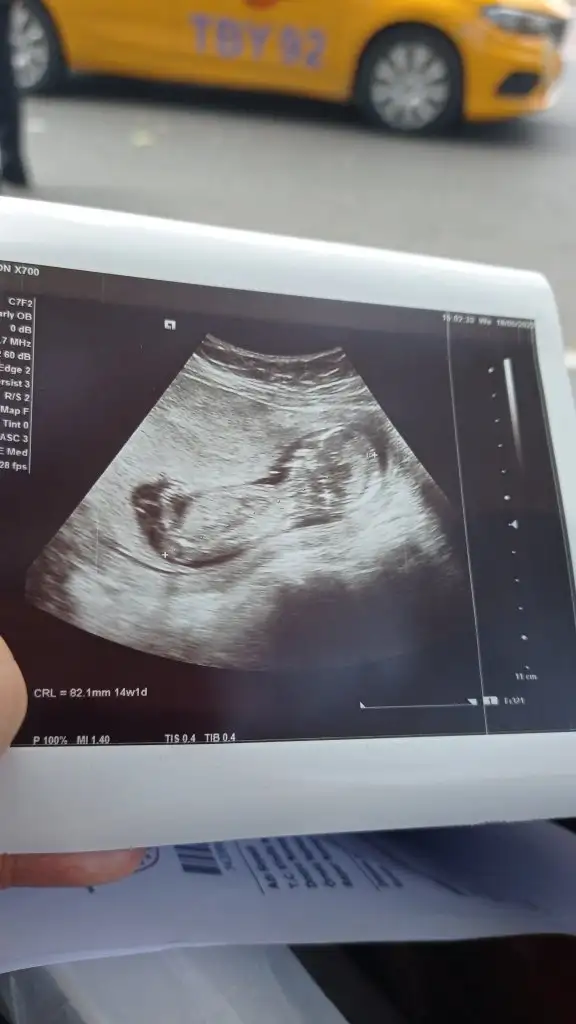

Cok anlamamakla beraber erkek gibi geldi bana saglikla gelsin bebeginizCinsiyet tahmini yapabilirmisiniz 14 haftalik

Erkek görünüyor gibi en iyi 11 12 13 haftalar olmalıCinsiyet tahmini yapabilirmisiniz 14 haftalik